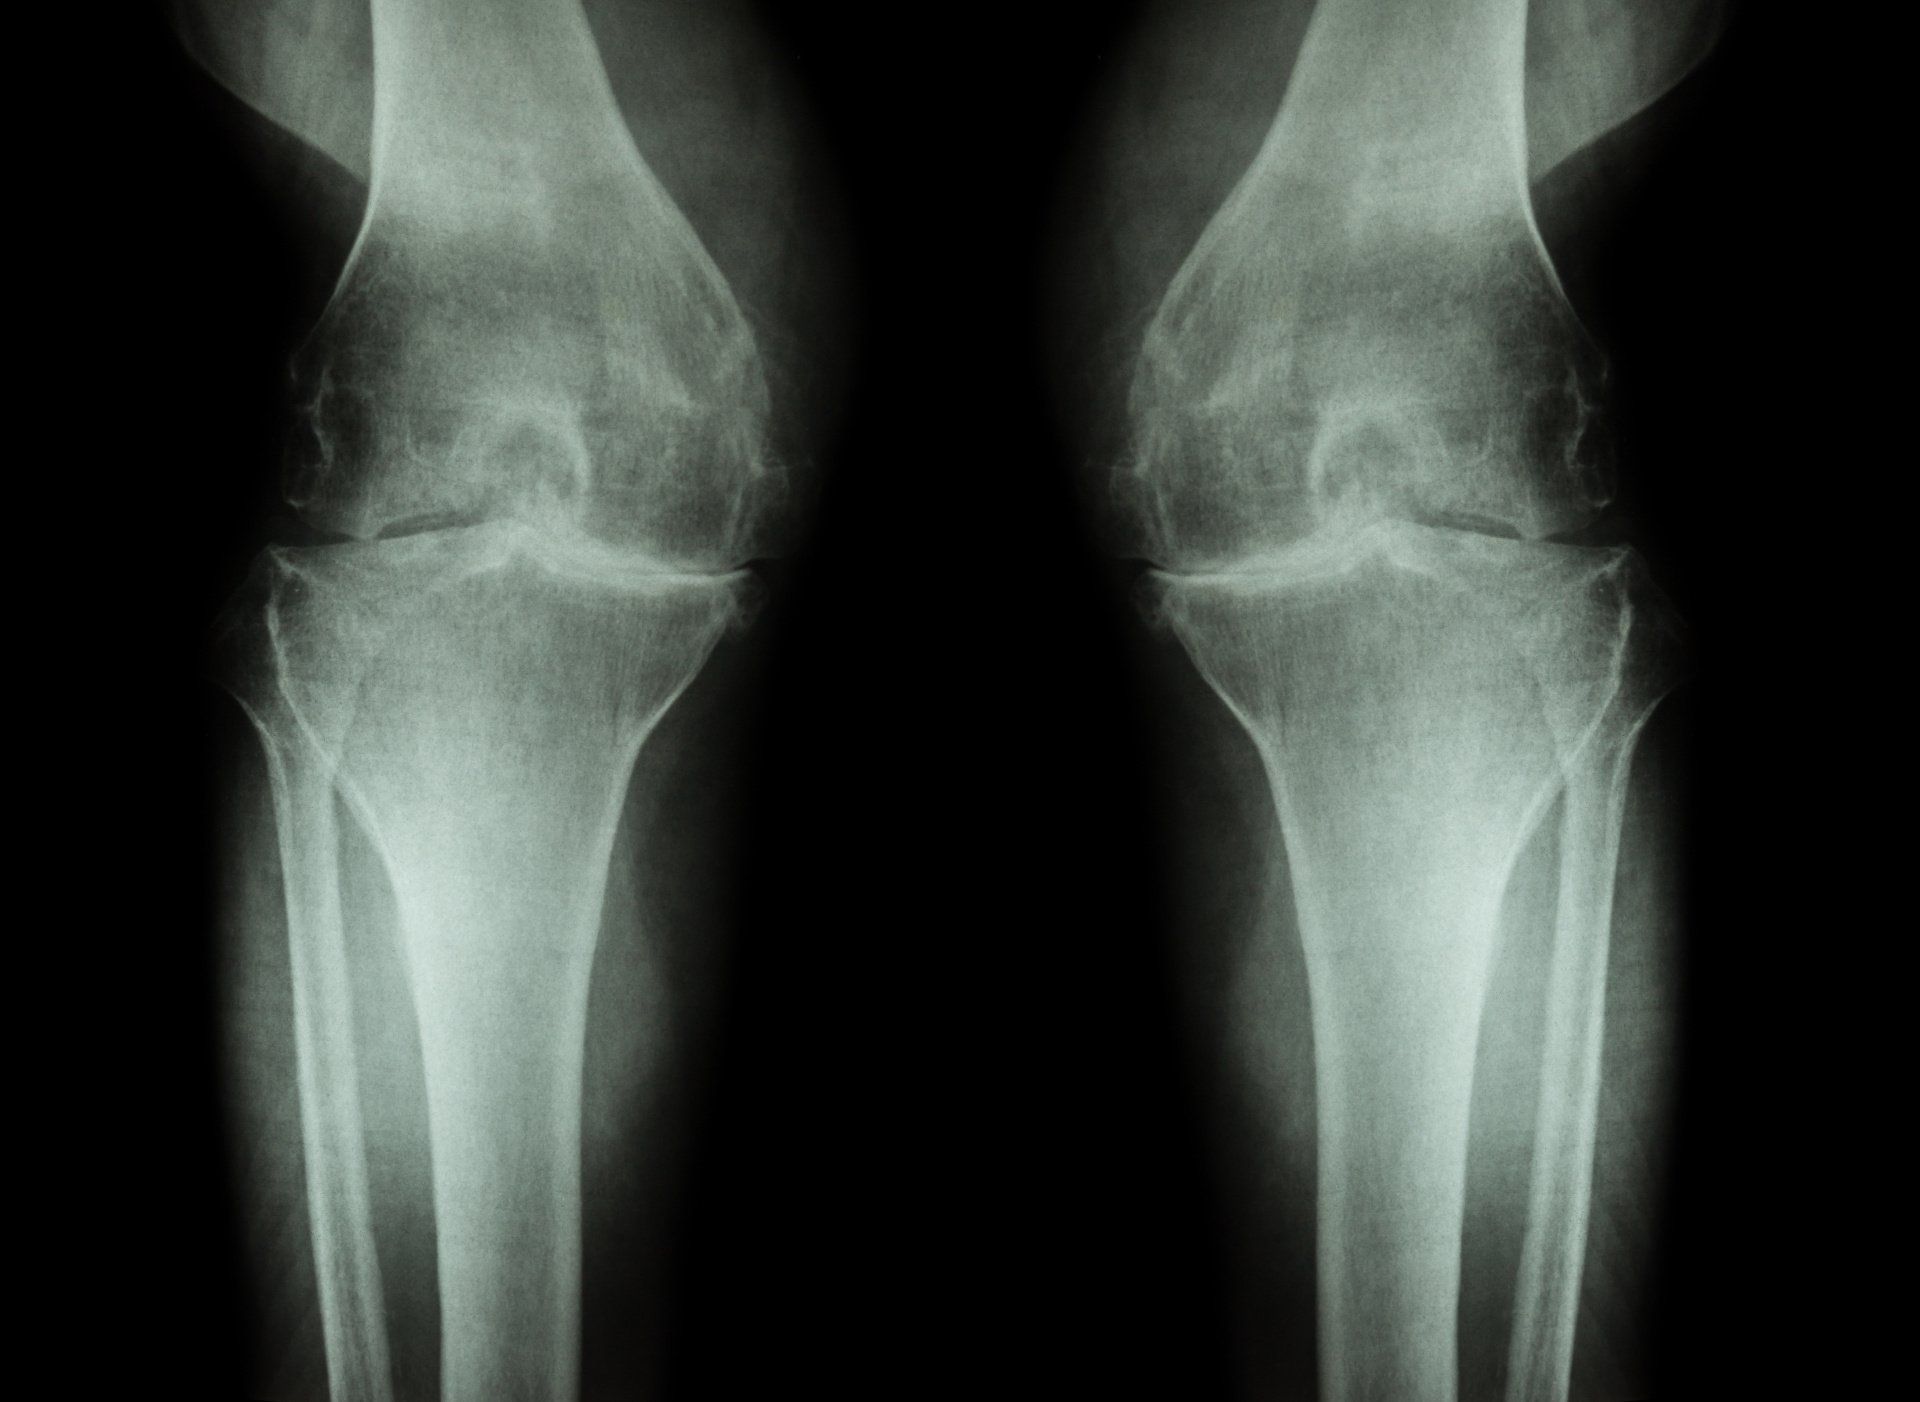

Ποια μέρη του γόνατος επηρεάζονται πιο συχνά;

- Η αρθρίτιδα του γόνατος μπορεί να είναι περιορισμένη σε ένα, δύο, ή και στα τρία μέρη του γόνατος

- Πιο συχνά επηρεάζεται το έσω μισό του γόνατος την οποίο δέχεται συνήθως 70% του φόρτου βάρος κατά την κίνηση

- Οστεοαρθρίτιδα της επιγονατιδομηριαίας άρθρωσης είναι συνήθης αλλά μπορεί να εμφανιστεί κι από μόνη της χωρίς τα άλλα δύο μέρη του γόνατος να έχουν φαγωθεί